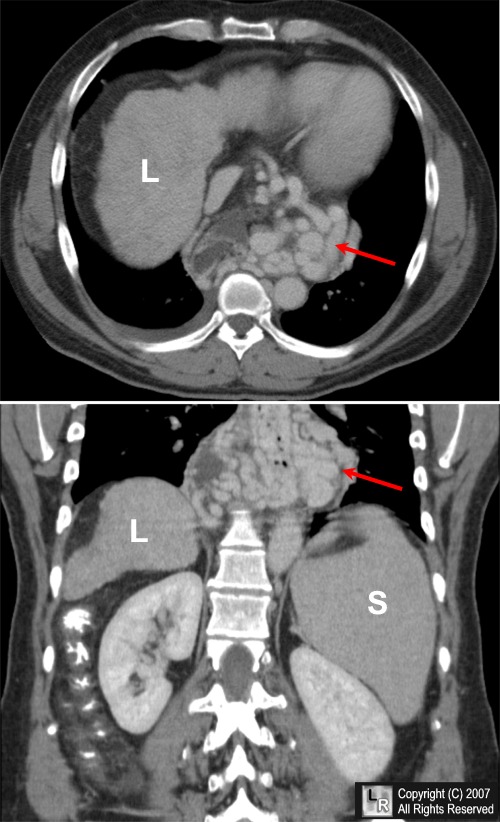

- CT

- Thickened esophageal wall and lobulated outer contour

- Scalloped esophageal luminal masses

- Right- / left-sided soft-tissue masses = paraesophageal varices

- Marked enhancement following dynamic CT

Esophageal varices. An enhanced axial (top) and coronal reconstruction CT scan of the upper abdomen shows markedly tortuous and dilated varices surrounding the lower esophagus. The liver (L) is small and nodular from cirrhosis and the spleen (S) is enlarged from portal hypertension.